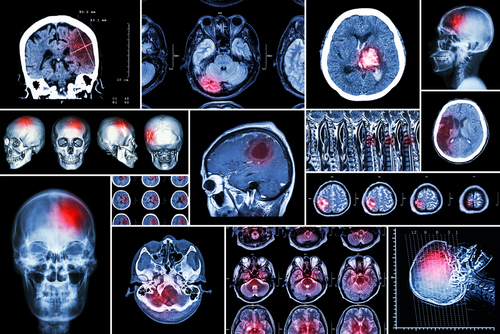

USC-led team has archived and shared hundreds of brain scans from stroke patients, which researchers hope will help to forecast which patients will respond to a variety of rehabilitation therapies.

Stroke is the leading cause of disability in adults, affecting more than 15 million people worldwide each year, according to the World Health Organization. During a stroke, blood flow to part of the brain is cut off. Without oxygen, brain cells die and cease to function. The damaged area, known as a lesion, is what researchers and clinicians study as they design, test, and implement recovery programs. Typically, neuroanatomy experts manually draw boundaries around the lesions—in a process called segmentation—but researchers hope to automate this practice so they can examine more images.

“We can’t do it by hand at the scale of thousands, so we are really interested in helping find better automated ways, using machine learning and computer vision, to identify the lesions and have machines draw those boundaries.”